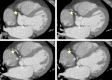

Figure 2.

Figure 2.. Coronary computed tomography angiography (CCTA) with right coronary artery marked by green outlined star and left coronary artery marked by asterisk symbol